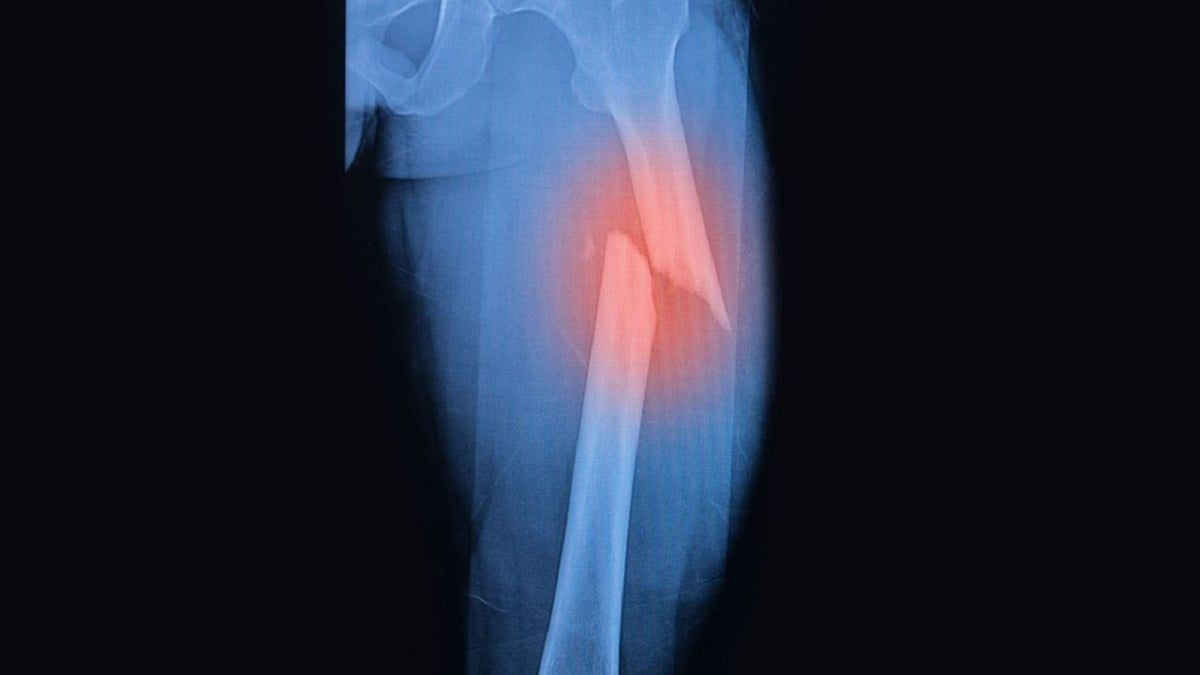

محمد الرخا - دبي - الاثنين 22 أبريل 2024 01:06 صباحاً - كشف علماء يابانيون عن تقنية جديدة لشفاء العظام المكسورة، لا تسرع عملية التعافي فحسب، بل تعزز أيضًا قوة العظام بأكثر من ثلاثة أضعاف.

وباستخدام تقنية تشعيع البلازما، فإن النهج المبتكر يحمل وعدًا بإحداث ثورة في علاج الكسور المعقدة، بحسب تقرير نشره موقع Good News Network.

فمن خلال تسخير بلازما الضغط الجوي غير الحراري، وهي تقنية تكتسب زخمًا في الأوساط الطبية لقدراتها على إصلاح الأنسجة، سعى الفريق إلى معالجة فترات الشفاء الطويلة المرتبطة بالكسور النازحة أو المعقدة التي غالبًا ما تتطلب إجراء عملية جراحية وفترات تثبيت طويلة.

وبمقارنة مجموعتين من الحيوانات، إحداهما تعاني من كسور قياسية والأخرى تعاني من كسور غير ملتحمة تتميز بتأخر الشفاء أو عدم اكتماله، لاحظ الباحثون أن تشعيع البلازما ساهم بشكل كبير في تسريع الشفاء في المجموعة الأخيرة.

وعلاوة على ذلك، تجاوزت قوة المناطق الملتئمة في الكسور المشععة قوة الكسور غير المشععة بنحو 3.5 مرة. ويؤكد هذا التحسن في قوة العظام الإمكانات التحويلية لطريقة العلاج الجديدة.